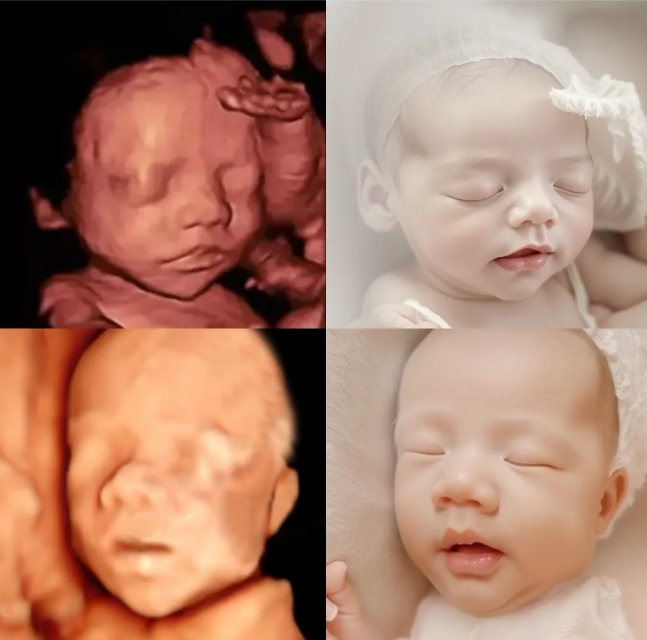

在众多孕期产检项目中,准爸妈们期待的项目一定有四维彩超,宝宝长得像爸爸还是妈妈?单眼皮还是双眼皮?小鼻梁挺不挺?

四维AI照,是洛阳白马医院为孕期宝妈提供的一项增值服务,利用人工智能算法,大致绘制宝宝出生后的模样。

通过四维彩超中宝宝的脸型,头型,五官位置等信息,利用人工智能算法,可以大致测算并画出宝宝的样子,预测宝宝出生后的长相,让父母提前预知宝宝的模样,满足准爸妈们的好奇心。

不过呢,宝宝的长相受多种因素的影响,四维宝宝AI照,仅供娱乐参考哦!